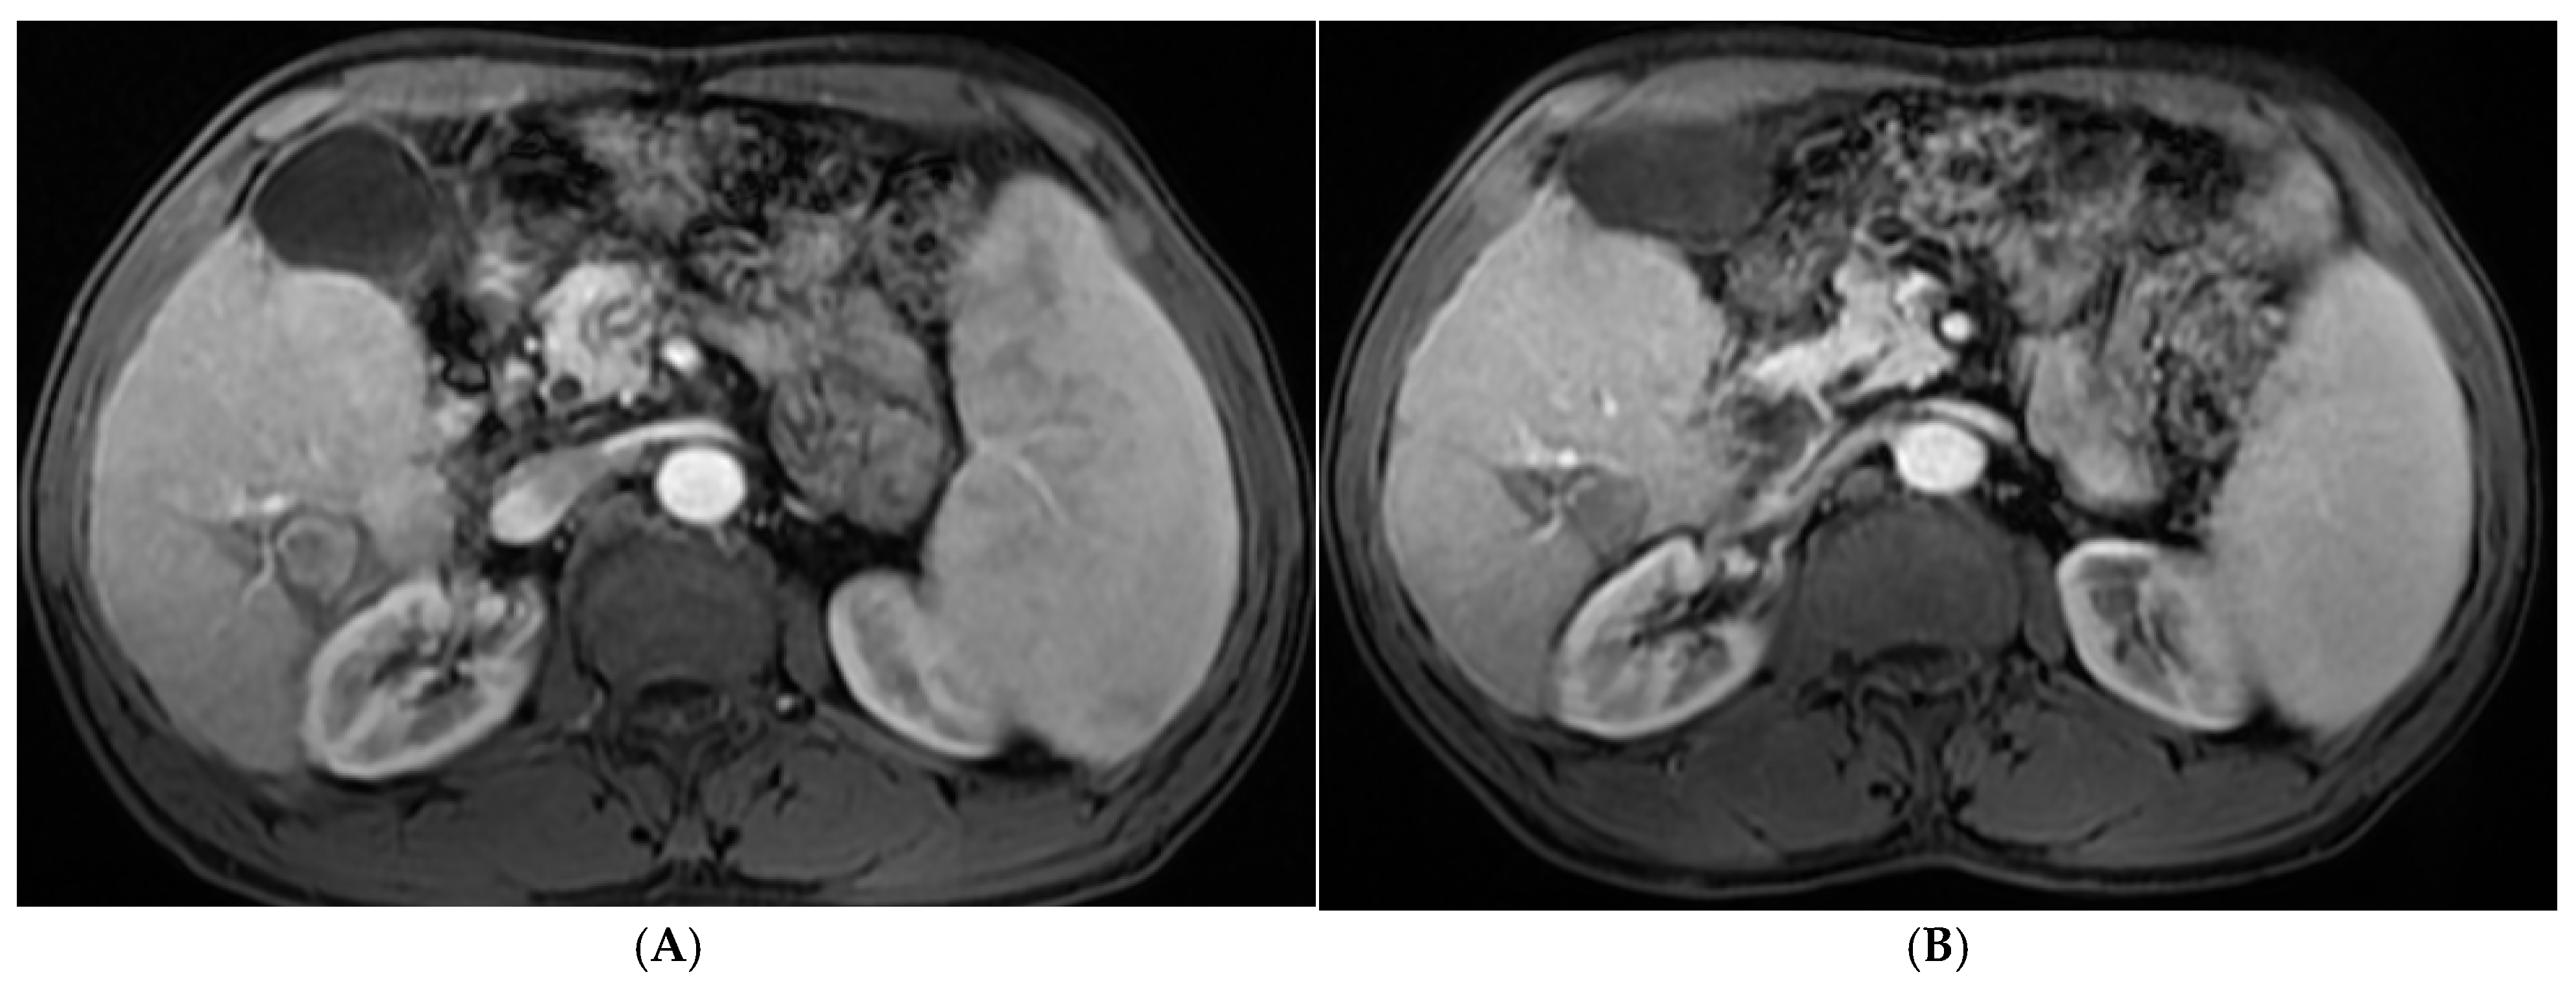

2.2.2. Procedures